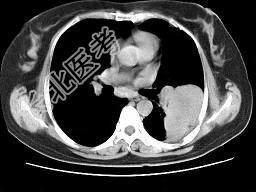

- 单项选择题女,52岁, 左侧背痛一月,胸部CT如图, 最可能的诊断为 ( )

A、左肺中央型肺癌

B、左肺周围型肺癌

C、左肺感染

D、左肺炎性假瘤

E、肺隔离征